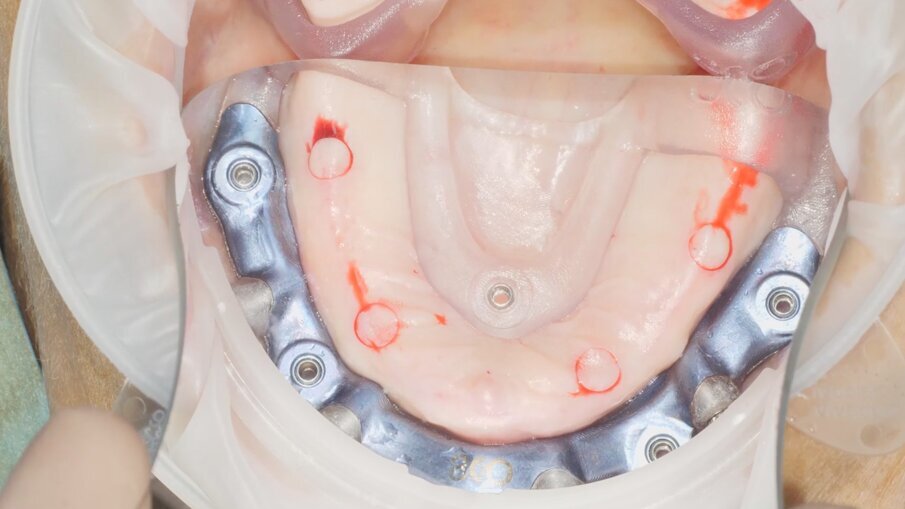

Veniamo quindi al posizionamento della protesi mediante carrier, a sua volta ancorato agli stessi punti di fissaggio della dima base. È significativo osservare come la stabilizzazione della sola vite palatale consenta l’allineamento perfetto tra i sistemi di fissaggio (Fig. 22), mentre il dettaglio mostrato in Fig. 24 illustra efficacemente come prima della cementazione della protesi l’accoppiamento e la centratura del foro protesico appaiano perfetti, confermando quindi come l’obiettivo di alloggiamento della protesi nella sede prestabilita sia stato colto. Per la fase di cementazione con cemento duale si è prestata attenzione alla realizzazione di un foro aggiuntivo per permettere al materiale di raggiungere gli abutment. I fori di accesso alle viti vengono tappati con filo di teflon (Figg. 25, 26) ed è a questo punto possibile andare a fissare la protesi e rimuovere il sistema carrier (Fig. 27). Lasciamo la dima in posizione, così che nell’eventualità in cui un abutment non dovesse essere stato cementato correttamente, ci riserviamo la possibilità di riprendere il posizionamento strategico dell’intero sistema Pcube, intercettando possibili impedimenti alle manovre di finalizzazione del caso.